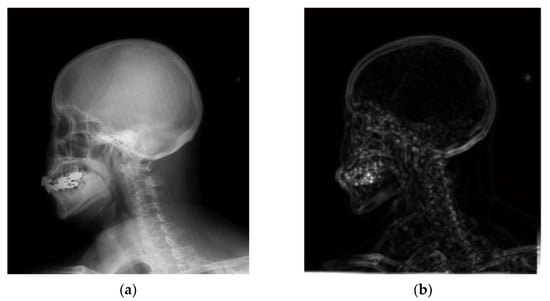

4.1. Simulations for Multicale Diagnostic Detail Enhancement on DR Images

4.2. Simulations for Multiscale Noise Reduction in DR Images